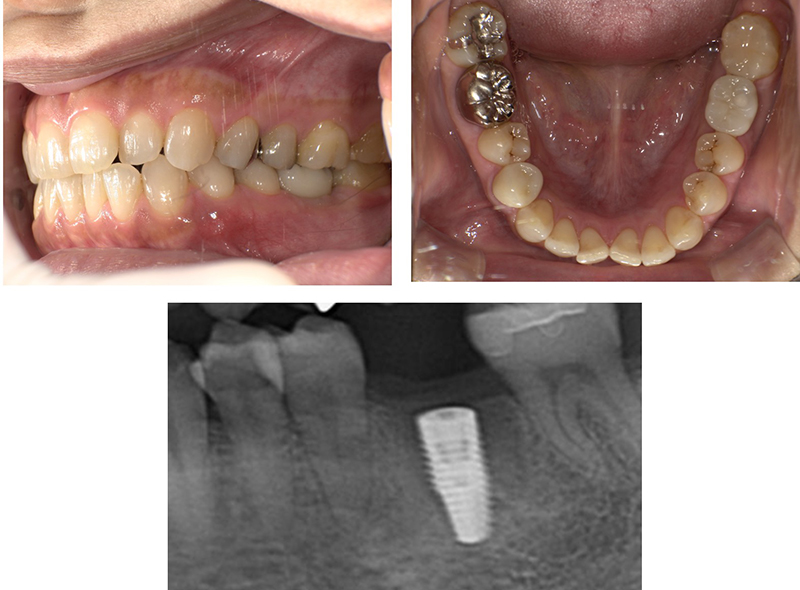

症例紹介

-

before

after

| 年齢・性別 | 47歳・女性 |

|---|---|

| 主訴 | 時々腫れるということで来院。歯根破折を認め、抜歯適応となった。欠損部分のインプラントを希望。 |

| 治療内容 | 抜歯を行い骨ができるのを待って、3ヶ月後インプラント体を埋入。更に2ヶ月後、2次オペを行い、インプラント体と骨の結合を確認したのち被せ物の型取りを行った。 その後、最終補綴物を装着した。 |

| 治療期間 | 約半年(9回) |

| 費用 | インプラント体:330,000円(税込み) 補綴物(ジルコニア)132,000円(税込み) コラーゲン使用吸収性局所止血材:4,400円(税込み) |

| リスク・副作用 | インプラント手術後は反応性の出血・腫れ・あざがでる場合がありますが、時間の経過とともに治ります。保険適応外なので、自由診療となります。 |